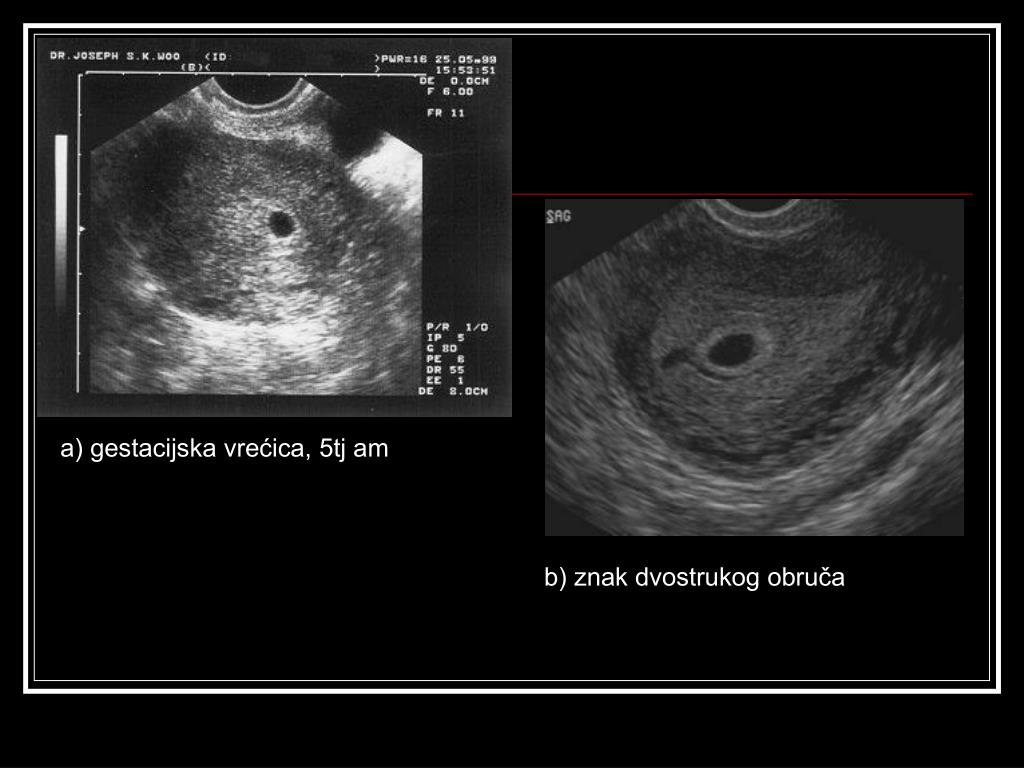

12. a) gestacijska vrećica, 5tj am b) znak dvostrukog obruča

11. Najraniji UZV dokaz normalne intruterine trudnoće • GESTACIJSKA VREĆICA u prednjem ili stražnjem listu zadebljalog endometrija- asimetrično smještena unutar materišta, znak „dvostrukog obruča“. • Najraniji prikaz transvaginalnim UZV- u 4 tj amenoreje (GV oko 2-3mm): beta hCG 500- 800 (1000-1500) mIU/l= DISKRIMINACIJSKA RAZINA beta hCGa • u 10tj amenoreje GV se ne prikazuje